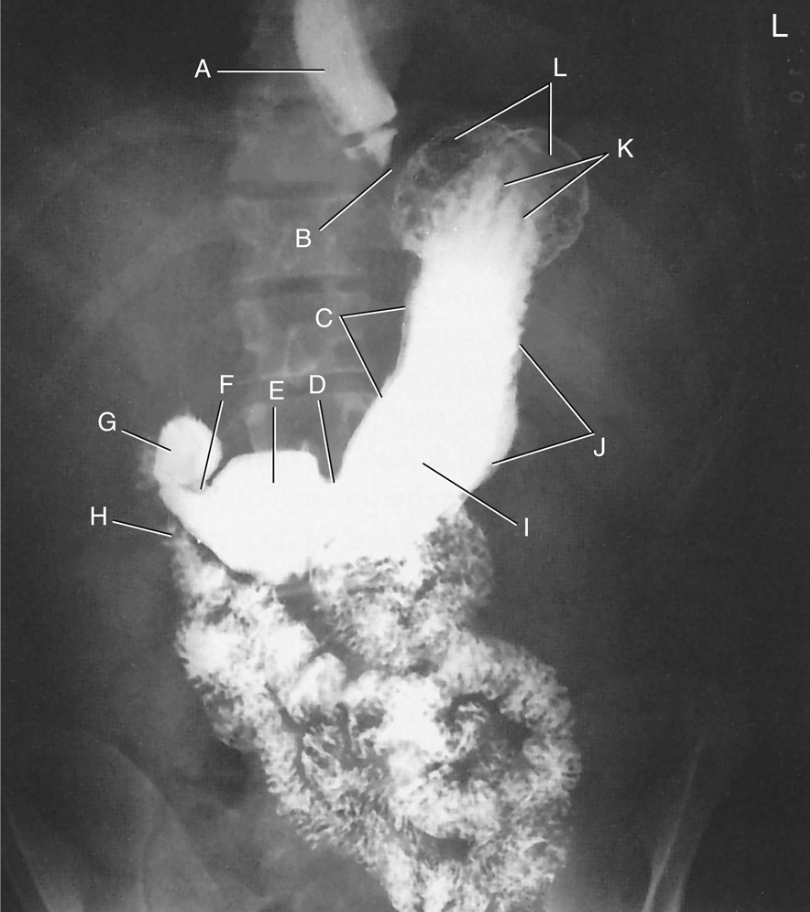

Label

Right lobe

Left lobe

Gallbladder

Falciform ligament

Caudate lobe

Inferior Vena Cava

Quadrate lobe

Common Hepatic Duct

Common Bile Duct

Liver

Cystic Duct

Duodenum

Right Hepatic Duct

Left Hepatic Duct

Pancreatic Duct (Duct of Wirsung)

Hepatopancreatic Ampulla (Ampulla of Vater)

Descending Duodenum

Esophagogastric junction

Cardiac notch

Fundus

Body

Greater curvature

Pyloric portion

Pyloric antrum

Pyloric canal

Pyloric orifice

Angular notch

Lesser curvature

Cardiac antrum